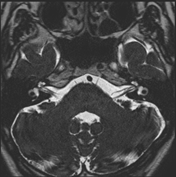

图4:3D TSE结合DRIVE,组成3D TSE DRVIE序列,TR仍然为1500ms

将前面的3D TSE序列结合DRIVE技术组成3D TSE DRIVE序列,TR仍然设置为1500ms,可以发现液体的信号强度有所增加了。